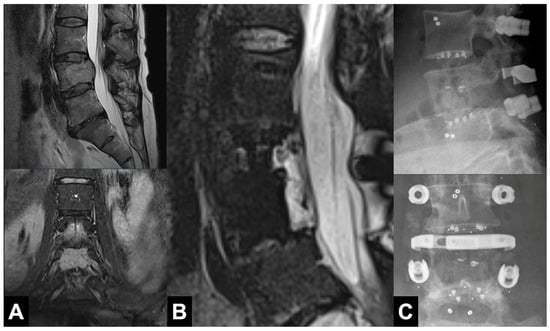

3.2. Radiographic Outcomes

3.3. Clinical Outcomes

4.3. Osseointegration and Fusion Rates